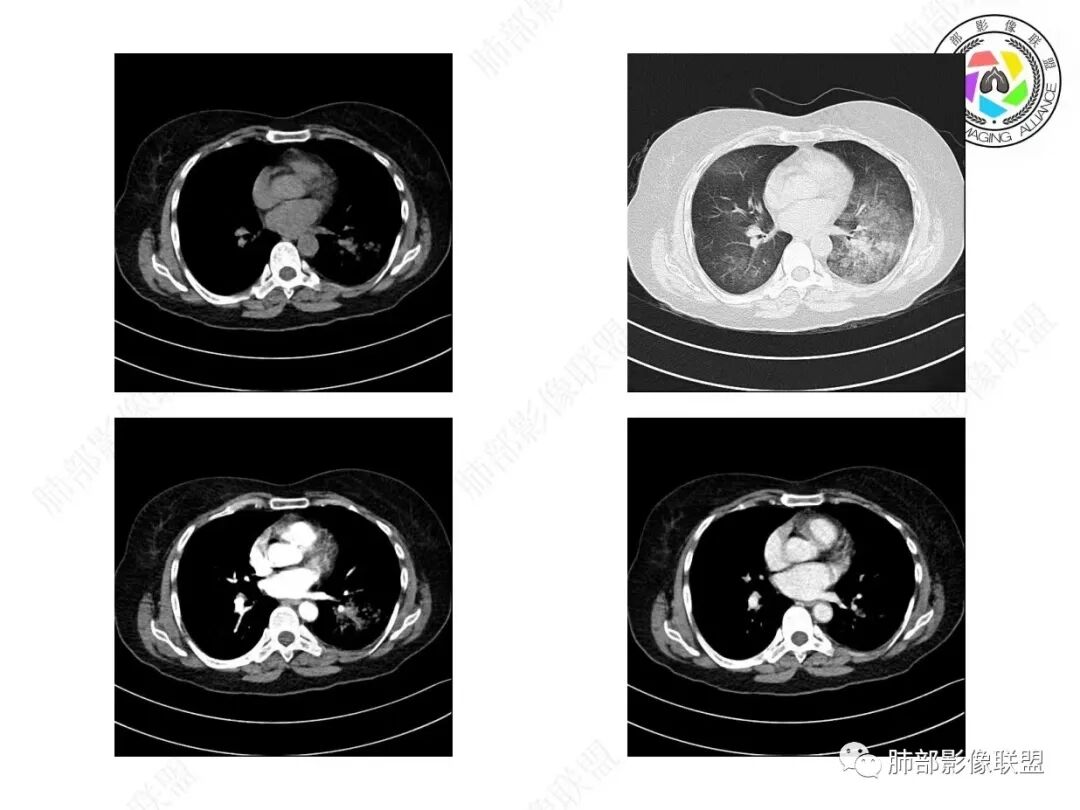

宇宙:两肺多发磨玻璃影,边缘模糊,左肺为著,左肺下叶伴实变,增强实变不均匀强化,其内支气管有阻塞、扩张,考虑粘液腺癌。

飞鹰行动:病史较长,左肺下叶实变及周围磨玻璃影,增强可见血管造影征,考虑左肺下叶粘液腺癌。

放射线:左肺下叶实变及双肺磨玻璃影,左下肺病灶周围磨玻璃影,有重力作用,呈叠瓦片状,增强可见血管造影征,考虑左肺下叶粘液腺癌伴双肺播散。

放射小白:中年女性,间断咳嗽一月余,咳痰4天;影像表现:右肺中下叶、左肺下叶见磨玻璃密度影,左肺下叶局部可见实性密度影,实性成分内部可见变窄、截断支气管通气征,增强实性成分内部可见血管造影征,但是血管扭曲,结合以上分析两肺符合肺黏液腺癌,不排除肺腺癌。

患者,女性,57岁。咳嗽1月、咳痰4天,亚急性病史,抗炎效果不佳,体温不高,痰为白色黏痰,白细胞稍高,主病灶在左下叶,实变+GGO,其余肺也有GGO,伴随有结节。

本例病例老年女性,慢性病程,抗炎效果不佳。CT示左肺下叶实变影,周围可见大片磨玻璃密度影,密度不均。右肺亦见少量斑片状磨玻璃密度影。增强可见血管造影征,结合南大分析,排除真菌,结核等,答案就呼之欲出了。